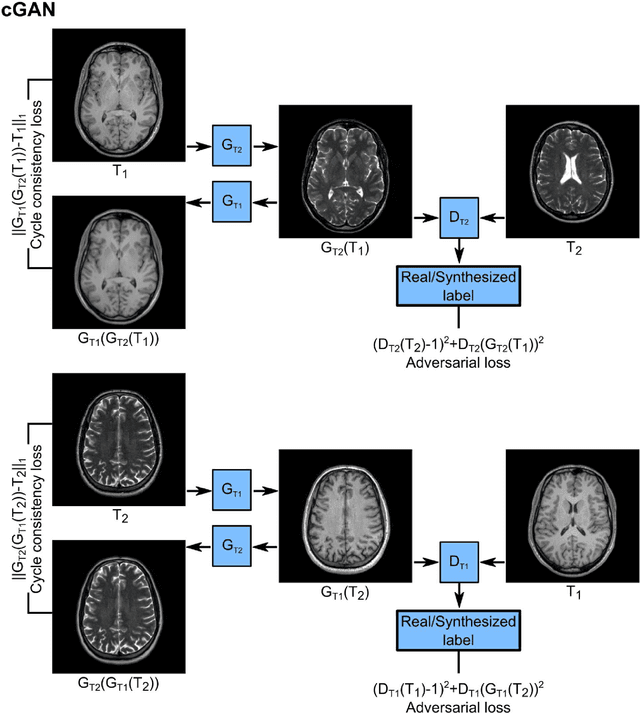

Abstract:Acquiring images of the same anatomy with multiple different contrasts increases the diversity of diagnostic information available in an MR exam. Yet, scan time limitations may prohibit acquisition of certain contrasts, and images for some contrast may be corrupted by noise and artifacts. In such cases, the ability to synthesize unacquired or corrupted contrasts from remaining contrasts can improve diagnostic utility. For multi-contrast synthesis, current methods learn a nonlinear intensity transformation between the source and target images, either via nonlinear regression or deterministic neural networks. These methods can in turn suffer from loss of high-spatial-frequency information in synthesized images. Here we propose a new approach for multi-contrast MRI synthesis based on conditional generative adversarial networks. The proposed approach preserves high-frequency details via an adversarial loss; and it offers enhanced synthesis performance via a pixel-wise loss for registered multi-contrast images and a cycle-consistency loss for unregistered images. Information from neighboring cross-sections are utilized to further improved synthesis quality. Demonstrations on T1- and T2-weighted images from healthy subjects and patients clearly indicate the superior performance of the proposed approach compared to previous state-of-the-art methods. Our synthesis approach can help improve quality and versatility of multi-contrast MRI exams without the need for prolonged examinations.